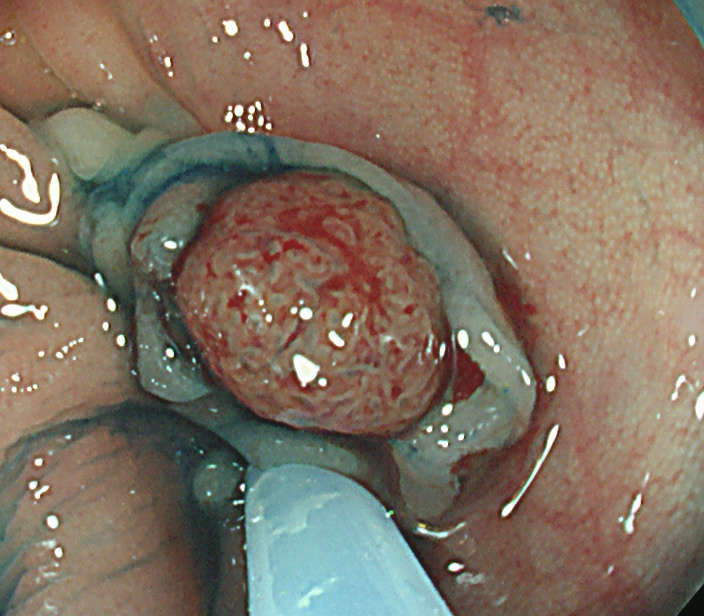

実際の「Extended Cold法」の模様を紹介します

しかしながら・・・いつも、このような綺麗な「目玉焼き」ができる訳ではありません。実際はスネアー(ワイヤー)が、うまくかからずに「分断」「分割」になったり、カンシ(ジャンボ・バイオプシー)を併用することも多いです。